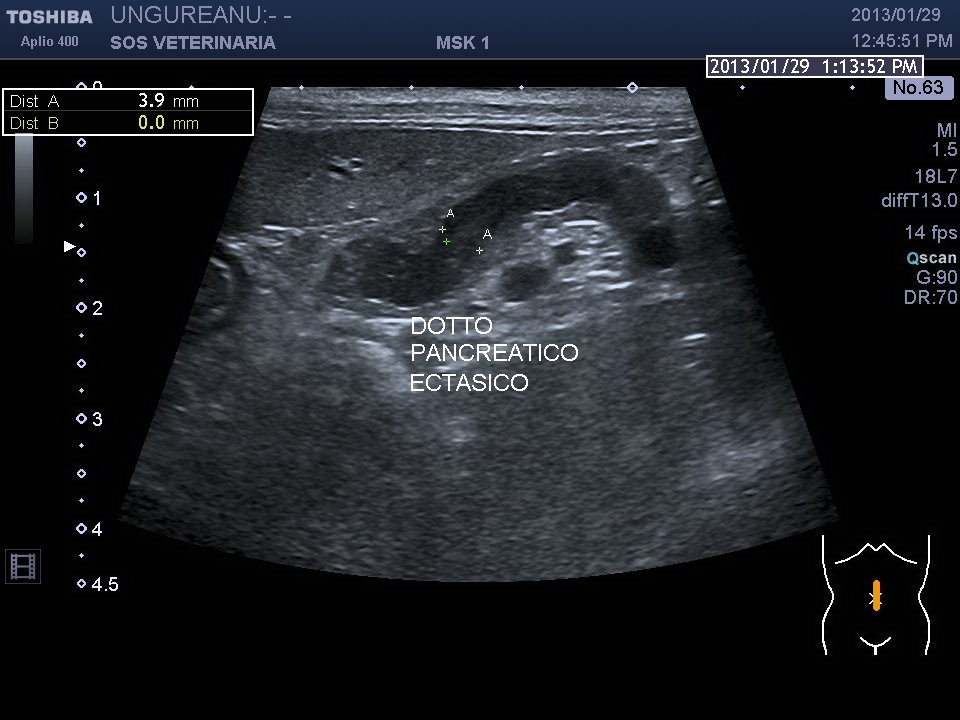

Rispetto il precedente caso la paipilla duodenale  e’ normale nella forma e nelle dimensioni ,sebbene affetto da calcolosi non si visualizzano calcoli nel coledoco o a livello della papilla che giustifichino la dilatazione delle vie biliari extraepatiche e pancreatiche  ,colpisce l’ispessimento del duodeno (5 mm contro un v.n. di 2,5 )  l’ectasia del dotto pancreatico, la stasi del succo pancreatico  e la diffusa presenza di strutture nodulari isolate o confluenti riferibili tessuto linfatico iperplastico  con un infiltrato di immunoblasti predominante .

La distensione delle vie biliari e pancreatiche puo’ essere secondaria al processo infiltrativo duodenale o a complicanza infiammatoria -settica comune nella specie felina (vedi triatide)  ,le interazioni sono molteplici ,la stessa calcolosi risulta severa con aspetti di colastasi intraepatica. Questo soggetto avrebbe avuto bisogno di approfondimenti e da destinarsi ad approfondimenti oncologici ,purtroppo anche in questo caso i proprietari non hanno voluto dar seguito al naturale iter diagnostico e terapeutico che il caso imponeva .

mucosa duodenale incremento ecogenicita' pancreas e dotto ectasico principale